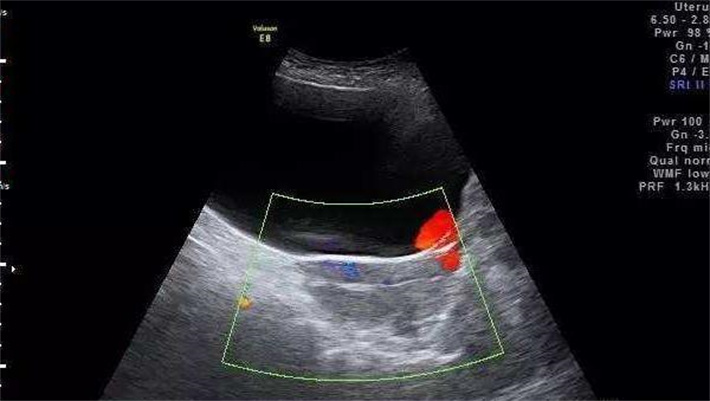

2.阴道B超检查

阴道B超用于观察子宫和卵巢的基础状态,包括子宫内膜厚度、形态、是否有息肉或肌瘤,以及双侧卵巢中基础卵泡的数量。通常建议在月经第2~3天进行,此时卵泡尚未发育,计数较为准确。如国内医院限制经期内检查,也可在月经干净后第7~8天完成。这份报告直接帮助医生预估促排卵的结果。